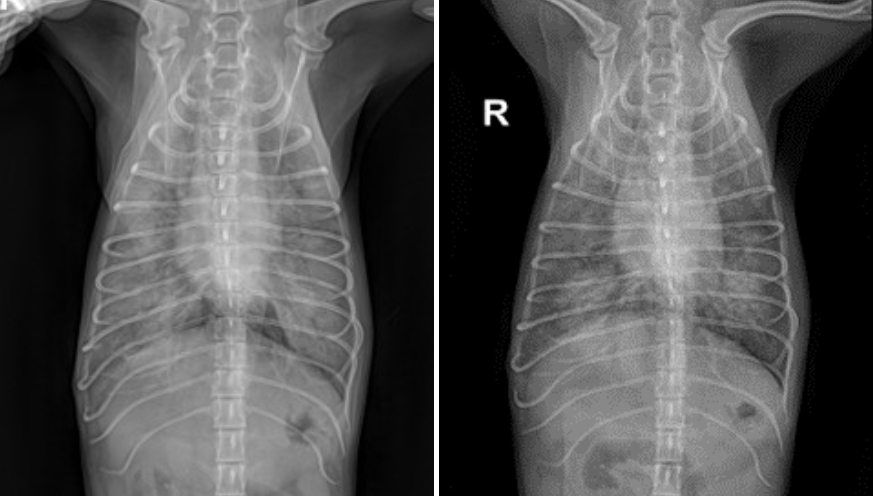

치료 2일차(좌) /치료 3일차(우)

입원 2일차, 테오는 호흡 상태가 점차 악화되었으며 방사선 검사상에서도 폐 상태가 이전보다 악화된 소견이 확인되었습니다.

새벽 시간대에 전반적인 상태가 급격히 나빠지며 응급 상황 가능성이 있어 보호자님 면회를 추가적으로 진행하였습니다.

이후 중환자실에서 산소 처치 및 치료 보강 등 집중 케어를 진행하였고, 다행히 입원 4일차부터는 호흡 상태가 점차 안정되면서 전반적인 컨디션이 빠르게 회복되는 모습을 확인할 수 있었습니다.